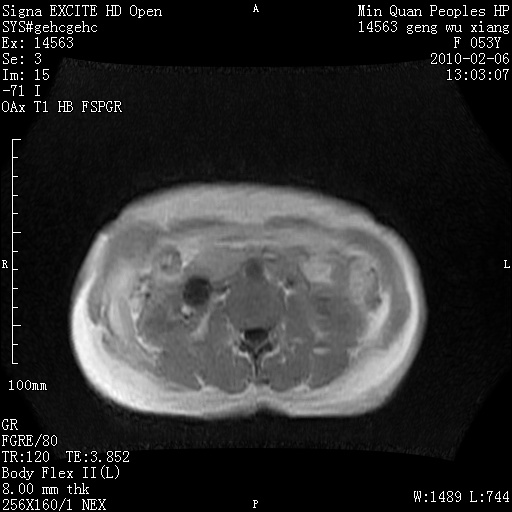

标题: MRI2762:胆道梗阻原因?

f,53y,全身黄染多日。

高位胆道梗阻 胆管癌可能性大

支持 高位胆道梗阻 胆管癌可能性大。